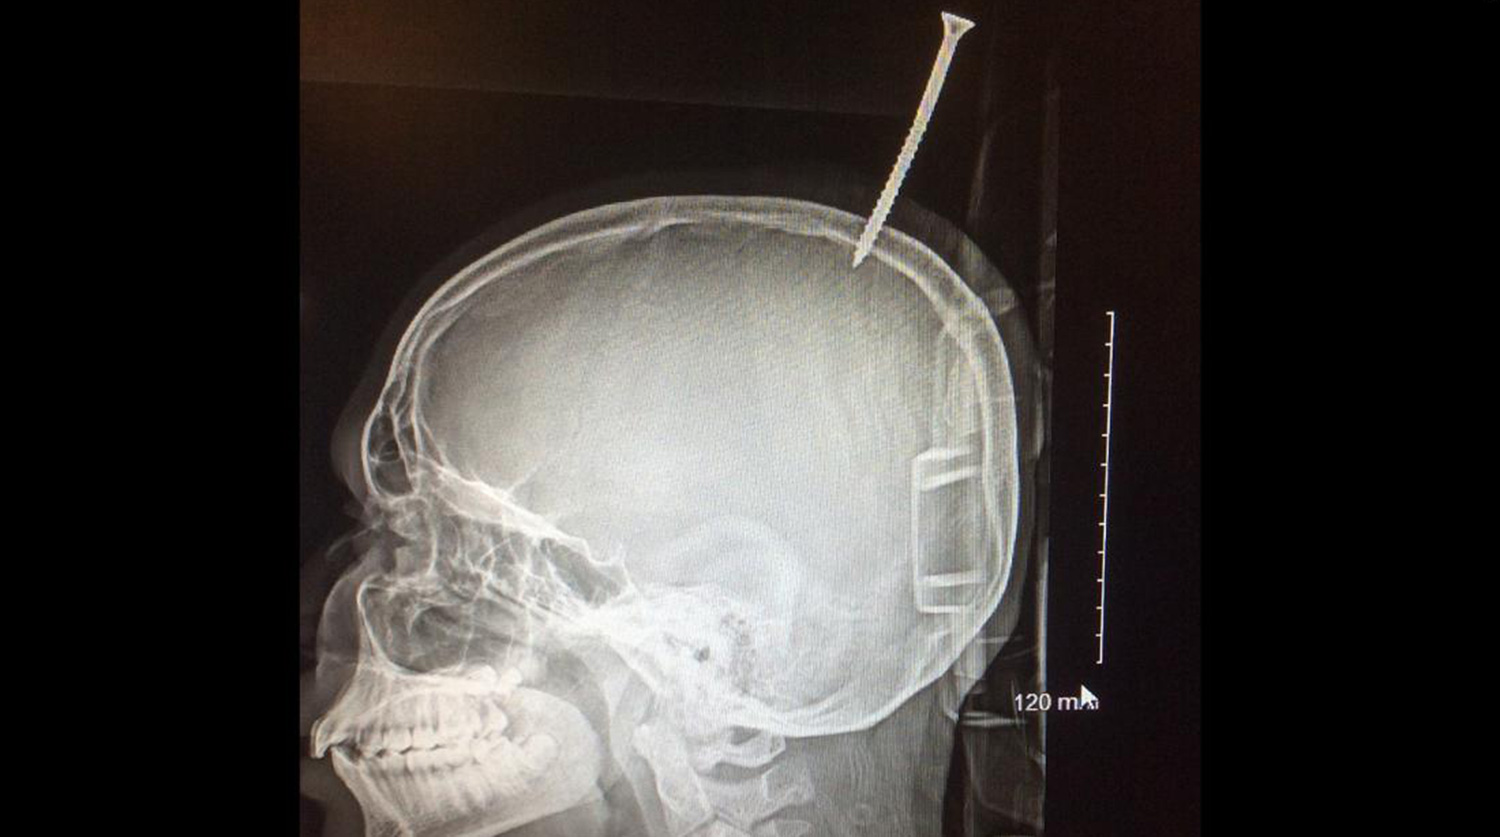

Нейрохирурги в США извлекли из черепа ребенка 15-сантиметровый шуруп

Нейрохирурги в США извлекли из черепа ребенка 15-сантиметровый шуруп — на голову мальчика свалилась доска. Врачи отмечают, что если бы шуруп отклонился хотя бы на миллиметр, мальчик бы погиб от кровотечения.

Семиклассник из США чудом выжил после того, как его голову пронзил 15-сантиметровый шуруп, вошедший в мозг. О необычном случае нейрохирурги рассказали каналу CNN.

13-летний Дариус Форман помогал двоюродным братьям строить дом на дереве, когда сорвался с ветки и упал на землю. Вслед за ним полетела и полутораметровая доска с 15-сантиметровым шурупом.

Когда мальчик поднялся, оказалось, что шуруп вошел в череп, прикрепив доску к голове.

Тетя быстро уложила мальчика на землю и вызвала медиков. Но даже они не сразу поняли, в каком опасном положении оказался Дариус. Шуруп не только повредил его череп, но и вошел в мозг в области верхнего саггитального синуса, крупной вены, расположенной между полушариями мозга и направляющими кровь от него к сердцу. Если бы шуруп пронзил вену, мальчик бы погиб от кровоизлияния.

«Еще бы миллиметр — и он бы истек кровью», — отмечает нейрохирург Алан Коэн.

После рентгена было решено отправить мальчика для операции в больницу Джонса Хопкинса в Балтиморе. Медикам пришлось одолжить вертолет у полиции — больничный оказался недостаточно большим.